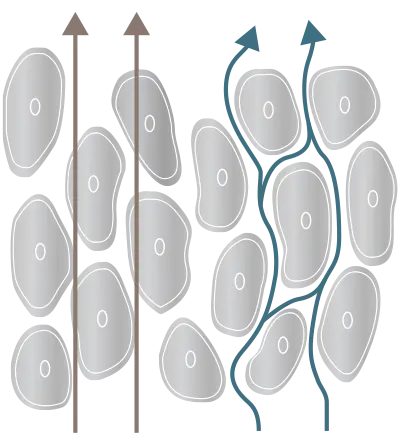

فناوری اندازه گیری

هرچه فرکانس بالاتر باشد، کنترل فرکانس در بدن انسان دشوارتر است که منجر به اندازهگیری امپدانس ناپایدار میشود. BWA بر این محدودیت غلبه کرد و اولین فرکانس 3 مگاهرتز جهان را به کار برد که حتی بهتر از غشای سلولی ما نفوذ میکند.